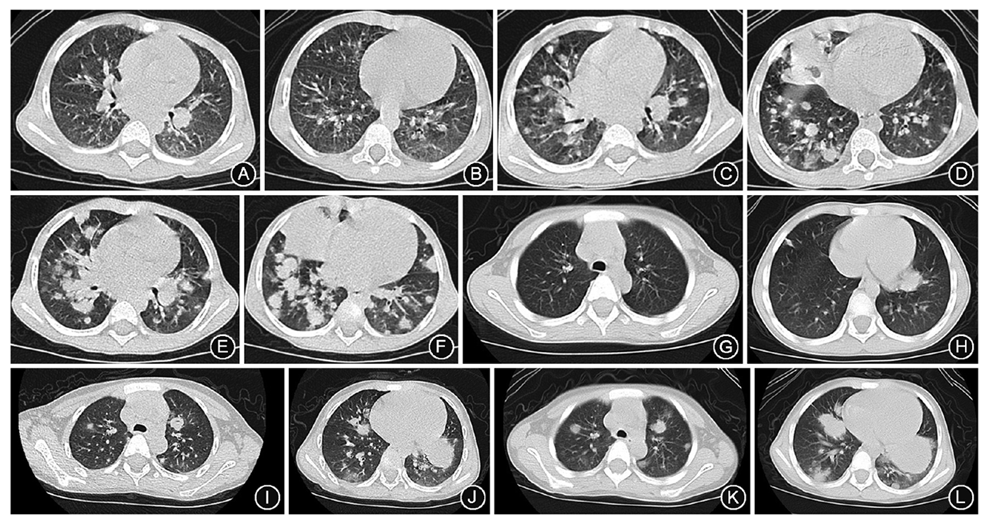

13例EBV+LPD患儿中男5例、女8例。中位年龄6.0岁(范围1.3~15.0岁),其中<3岁3例,3~5岁3例,6~11岁3例,12~14岁4例。确诊时5例病程小于3个月,其中最短1个月,最长24个月,中位病程3个月。5例以典型的IM症状起病,2例以单纯发热起病,2例以发热皮肤溃疡起病,另外4例的起病方式分别是发热伴腹部包块、发热伴抽搐、发热伴腹痛腹泻、发热伴皮肤出血点。13例均有发热,9例有肝、脾、淋巴结肿大,4例有淋巴结肿大而无肝、脾肿大;外周血2例出现三系降低,5例白细胞降低;7例肺受累,其中5例EB病毒阳性T细胞淋巴组织增殖性疾病(EBV+T-LPD)患儿表现为双侧肺间质受累,2例EB病毒阳性弥漫性大B细胞淋巴瘤(EBV+DLBCL)患儿表现为肺内结节状及团块状改变;3例中枢神经系统受累,表现有发热、头痛,其中1例出现抽搐,脑脊液检查均为无菌性脑膜炎表现,行头颅磁共振成像(MRI)检查无异常;3例心脏受累表现为冠状动脉增宽;3例肠道受累,表现为腹痛、腹胀、腹泻,其中1例出现肠穿孔;2例皮肤受累,表现为丘疹水疱样皮疹,合并溃疡,有痘疮样瘢痕形成,后期出现肝、脾、淋巴结肿大等全身症状;腹部包块1例,腹部MRI显示胰腺前下方肠系膜处不规则团块状异常信号影,范围为9.3 cm×8.2 cm×3.2 cm,包绕肠系膜上动静脉及其分支;2例出现噬血细胞综合征。13例患儿中,仅有1例家族史有一同胞哥哥在5月龄因巨细胞病毒肺炎死亡,其余12例均无明确或可疑的免疫缺陷家族史。

2例患儿诊断为EBV+DLBCL。例12为1岁10月龄幼儿表现为发热、颈部及腹股沟淋巴结进行性肿大,肺内病变由病初的多发点絮影及网格影进展为多发结节及实变(

值得注意的是本组病例中2例诊断为EBV+ DLBCL。EBV+ DLBCL常发生在老人年,与老年人的免疫功能减退相关,因此2008年WHO分型命名为老年人EBV+ DLBCL。后来报道EBV+DLBCL亦可以发生在青年人[11],故2016年WHO淋巴瘤分类已不强调年龄[2]。虽然该病为淋巴瘤,但由于发生发展与EBV感染密切相关,实际上,它是EB病毒阳性B细胞淋巴组织增殖性疾病的特定阶段,2008年EB病毒淋巴增殖性疾病国际分类会议将它归类为EBV+LPD的B细胞类型。本组2例患儿年龄分别为1岁10月龄和5岁1月龄,有关幼儿的EBV+DLBCL报道罕见报道。既往报道的青年人EBV+DLBCL均表现为淋巴结受累,包括颈部、纵膈、腹膜后、腹股沟等部位淋巴结受累,无淋巴节外器官受累[12,13,14,15]。不同于青年人的临床特征,本组2例患儿均以IM起病,疾病进展快,受累部位除淋巴结外,淋巴结节外受累显著,包括肺部、肠道等,尤其是肺部特征性病变为结节性病变,进行性增多、增大,均在病程3个月经病理活检确诊。老年人EBV+DLBCL亦经常累及淋巴结和结外器官,包括皮肤、扁桃体、肺、胃肠道等[16,17,18],与这2例患儿的临床表现相似。例12家族史有一同胞哥哥在5月龄因巨细胞病毒肺炎死亡,提示此类患者可能存在潜在未知的免疫缺陷,2例患儿还有以下共同特点:全血及血清的EB病毒-DNA持续增高,肺泡灌洗液EB病毒-DNA阳性,提示该病的发生发展与EB病毒感染密切相关。